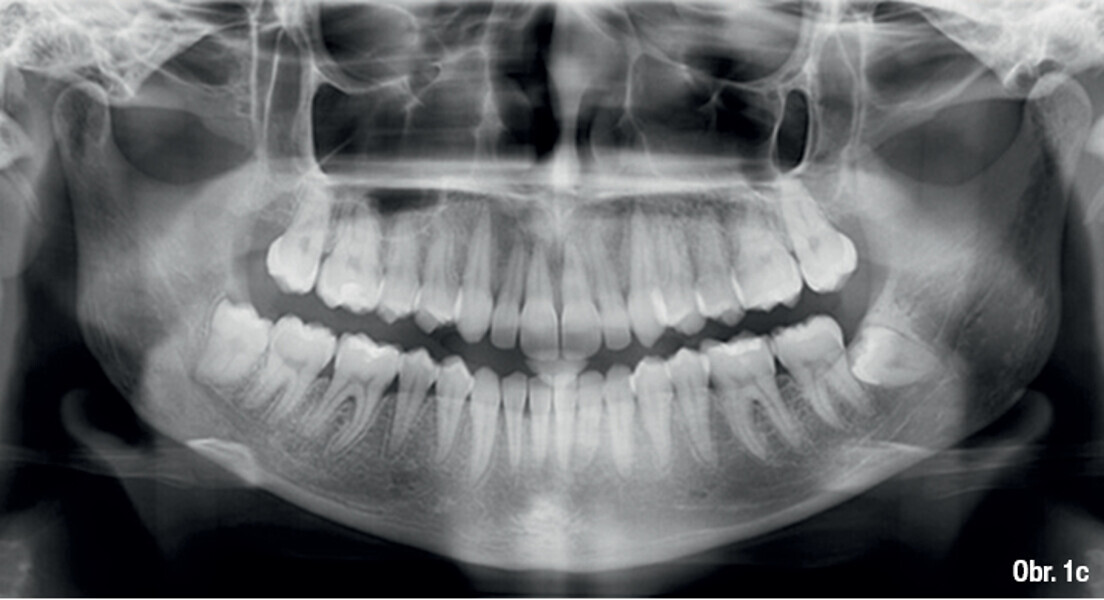

Distalizace horních molárů pomocí alignerů a cyklických sil